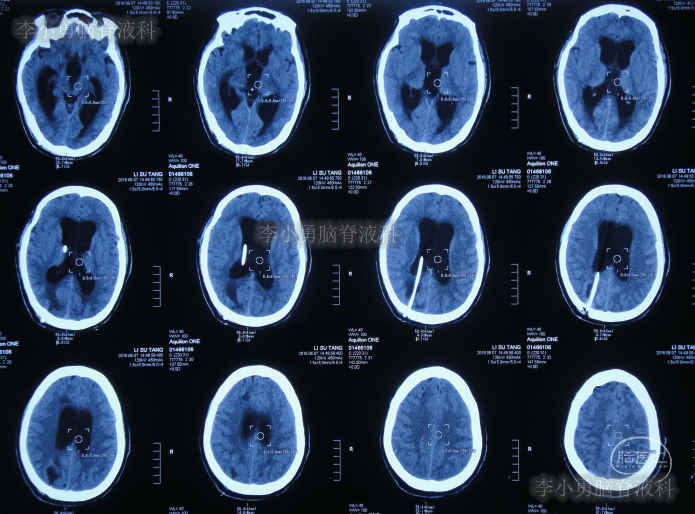

第三家医院第2次建议回家观察1周后即2016年4月3日,症状仍未缓解反而越来越重,于是,就诊于第四家位于上海市徐汇区的某三甲医院,查头颅CT后(图-2)“认为无明显异常”,怀疑癫痫。

图-2:2016年4月3日头颅CT

家属为进一步明确病因即2016年4月4日,第2次就诊并住入第二家的上海市静安区的某三甲医院,复查头颅影像后(图-3、图-4),给予按癫痫进行治疗。

图-3:2016年4月4日头颅CT